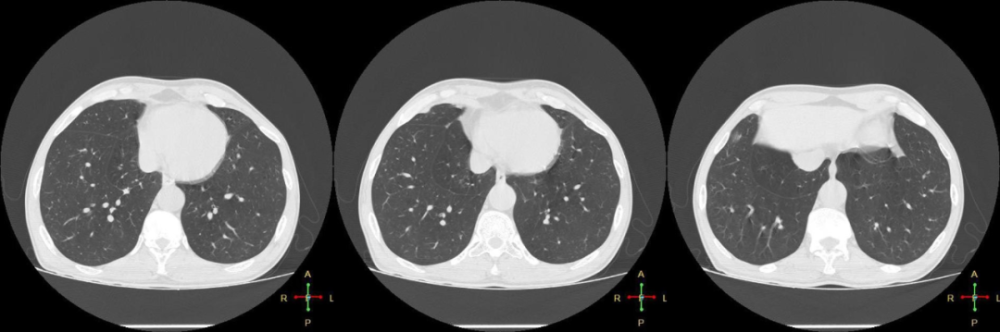

右肺有斜裂和水平裂,左肺则有斜裂.接下来我们来探讨一下肺裂.